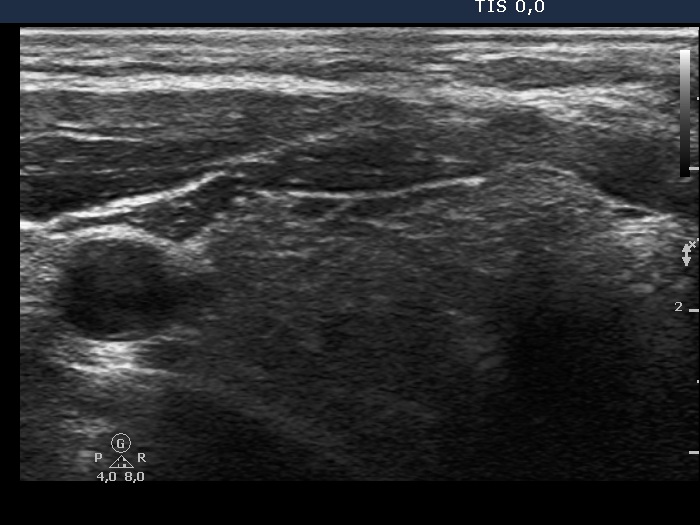

First examination (first row of images):

Clinical presentation: A 37-year-old man was referred for an evaluation of a 'lump in the throat' feeling.

Functional state: subclinical hypothyroidism with TSH 5.01 mIU/L, FT4 13.6 pM/L.

Palpation: the left lobe was suspicious containing a small nodule.

Ultrasonography. The thyroid was moderately hypoechogenic and displayed fibrosis. There was a relatively larger hypoechogenic lesion in the central part, and other smaller ones in the dorsal part of the left lobe. The dimensions of the largest lesion were 11x10x13 mm (width, depth, and length, respectively), the volume was 0.75 mL. The vascularization was not specific.

Aspiration cytology resulted in Hashimoto's thyroiditis. Atypia of unknown significance; the possibility of a Hürthle-cell tumor cannot be excluded.

We told the patient that the risk of malignancy is around 5%. We offered a follow-up examination instead of a surgery and suggested a repeat FNA in six months.